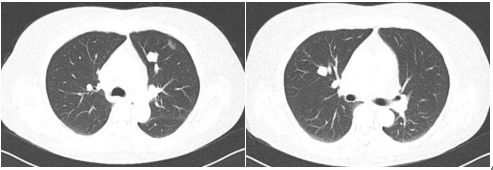

腹部增强CT(2020年9月):肝左叶巨大占位,考虑为肝细胞肝癌并门脉左支瘤栓可能。

1-3.png

图示:腹部增强CT(2020年9月)